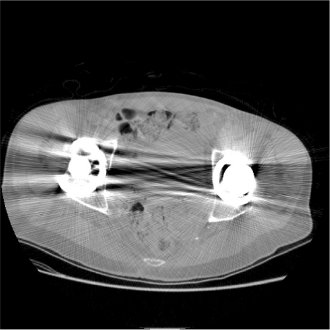

硬化伪影表现为高密度物质之间的暗带,通常产生于头部,也称 骨硬化 伪影,如图1. 左所示。骨硬化 伪影的另一种表现形式是骨-脑界面退化,边界模糊不清。

当扫描对象身体中具有其他高密度物质时,也会产生硬化伪影。如图1. 中,右所示1,为造影剂下小鼠肺部重建图和身体中有钛金属嵌入产生的硬化伪影重建图。

Fig 1. 硬化伪影